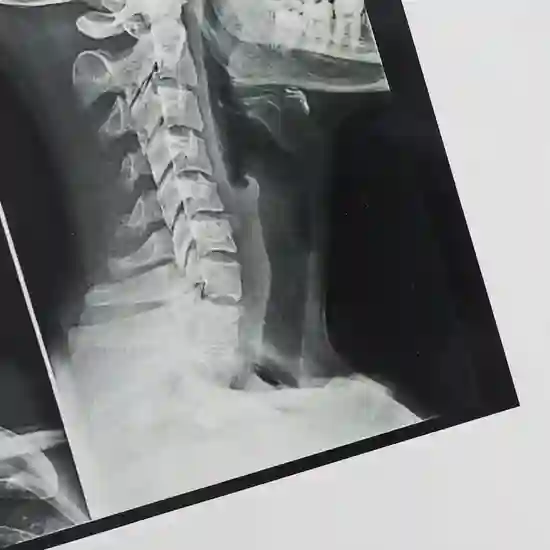

What is MRI Screening of the LS Spine?

A lumbar MRI looks at the lower part of your spine, where most back problems start.

Why is MRI Screening of the LS Spine done?

An MRI may be recommended to diagnose or treat spine disorders. Your condition could be caused by injury, illness, or infection. Symptoms of a lumbar MRI include: